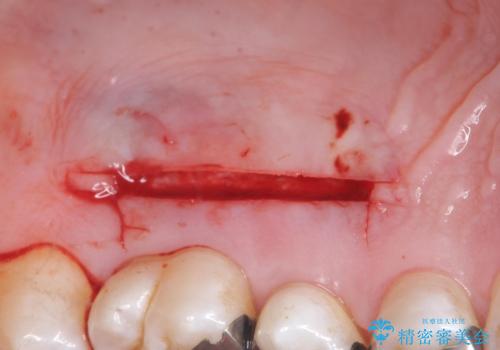

- 奥歯の歯茎が下がっていて(歯肉退縮)歯が染みるとのことで来院された患者様です。

退縮した歯茎に対して移植をすることで、しみる場所を覆う計画です。

歯根の分岐部よりも根尖側の頬側面が露出している状態でしたが、露出部位を分岐部までに抑えることができました。

しみる症状も改善され、大変喜んでいただけました。